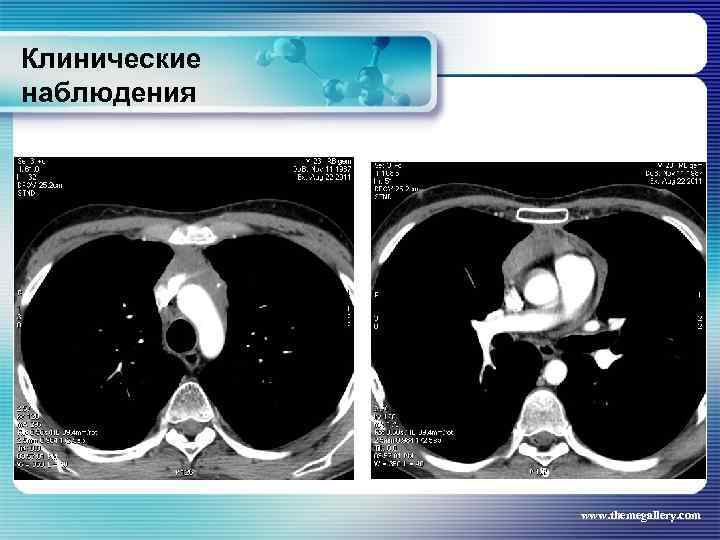

Клинические наблюдения Тот же пациент Был сформулирован клинический диагноз: Лифома Ходжкина, нодулярный склероз IV B стадия с поражением шейных, надключичных, подчелюстных, подмышечных, переднегрудных, парастернальных, паховых, внутригрудных, абдоминальных лимфатических узлов, печени, костного мозга, позвонков. В связи с выраженной нарастающей интоксикацией была начата терапия преднизолоном и первый цикл ВЕАСОРР. на этом фоне появились: резко повышенные показатели трансаминаз, асцит, массивные белковые отёки, сохранилась опухолевая интоксикация. Развилась аплазия гемопоеза. Доза преднизолона была увеличена. На этом фоне развилась полисегментарная грибковая пневмония. www. themegallery. com

Клинические наблюдения Тот же пациент Был сформулирован клинический диагноз: Лифома Ходжкина, нодулярный склероз IV B стадия с поражением шейных, надключичных, подчелюстных, подмышечных, переднегрудных, парастернальных, паховых, внутригрудных, абдоминальных лимфатических узлов, печени, костного мозга, позвонков. В связи с выраженной нарастающей интоксикацией была начата терапия преднизолоном и первый цикл ВЕАСОРР. на этом фоне появились: резко повышенные показатели трансаминаз, асцит, массивные белковые отёки, сохранилась опухолевая интоксикация. Развилась аплазия гемопоеза. Доза преднизолона была увеличена. На этом фоне развилась полисегментарная грибковая пневмония. www. themegallery. com